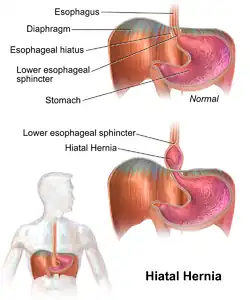

| A drawing of a hiatal hernia | |

A hiatal hernia or hiatus hernia[2] is a type of hernia in which abdominal organs (typically the stomach) slip through the diaphragm into the middle compartment of the chest.[1][3] This may result in gastroesophageal reflux disease (GERD) or laryngopharyngeal reflux (LPR) with symptoms such as a taste of acid in the back of the mouth or heartburn.[1][3] Other symptoms may include trouble swallowing and chest pains.[1] Complications may include iron deficiency anemia, volvulus, or bowel obstruction.[1]

The most common risk factors are obesity and older age.[1] Other risk factors include major trauma, scoliosis, and certain types of surgery.[1] There are two main types: sliding hernia, in which the body of the stomach moves up; and paraesophageal hernia, in which an abdominal organ moves beside the esophagus.[1] The diagnosis may be confirmed with endoscopy or medical imaging.[1] Endoscopy is typically only required when concerning symptoms are present, symptoms are resistant to treatment, or the person is over 50 years of age.[1]

Type I: A type I hernia, also known as a sliding hiatal hernia, occurs when part of the stomach slides up through the hiatal opening in the diaphragm.[11] There is a widening of the muscular hiatal tunnel and circumferential laxity of the phrenoesophageal ligament, allowing a portion of the gastric cardia to herniate upward into the posterior mediastinum. The clinical significance of type I hernias is in their association with reflux disease. Sliding hernias are the most common type and account for 95% of all hiatal hernias.[12] (C)

Type II: A type II hernia, also known as a paraesophageal or rolling hernia, occurs when the fundus and greater curvature of the stomach roll up through the diaphragm, forming a pocket alongside the esophagus.[11] It results from a localized defect in the phrenoesophageal ligament while the gastroesophageal junction remains fixed to the preaortic fascia and the median arcuate ligament. The gastric fundus then serves as the leading point of herniation. Although type II hernias are associated with reflux disease, their primary clinical significance lies in the potential for mechanical complications. (D)